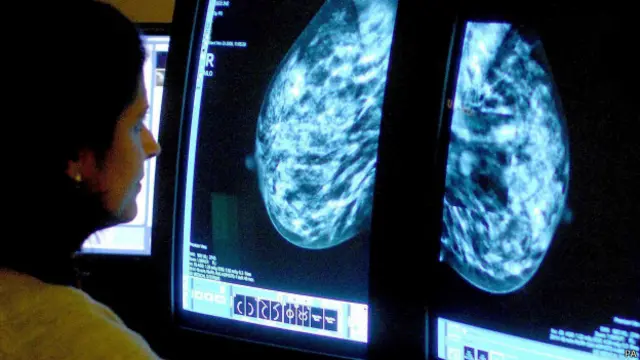

زیادہ تر ممالک میں خواتین میں سرطان کی سب سے زیادہ عام شکل چھاتی کا سرطان ہے، تاہم افریقہ کے بیشتر ممالک میں خواتین رحم کے سرطان (سروائیکل کینسر) میں مبتلا ہوتی ہیں۔